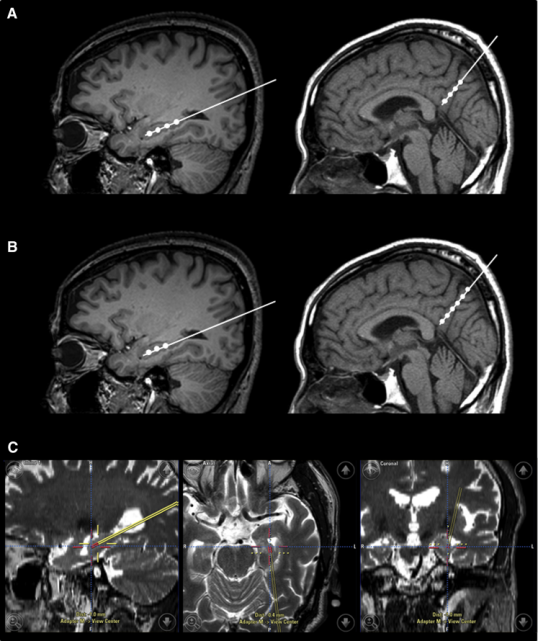

- 腦成像測試,如頭部CT掃描或頭部MRI

2015年,韓國首爾三星醫療中心招募了9名輕度至中度癡呆的阿爾茨海默氏病患者。Kim對9名患者進行了一項立體定向注射間充質干細胞的I期臨床試驗。

三名患者接受低劑量(1.0×107細胞/2 mL),6名患者接受高劑量(3.0×107hUCB-MSC 的細胞/2 mL) 。9名患者進行了三次干細胞注射(每隔4周一次)。

2a期試驗被命名為CLEAR MIND試驗,于2021年12月底開啟。實驗共納入了50位患者(49名接受治療),年齡在60-85歲之間,按美國國立衛生研究院-阿爾茨海默氏癥協會(NIA-AA)的標準,他們都是輕度阿爾茨海默氏癥患者。

這一次,研究測試了三種劑量的Lomecel-B與安慰劑,主要測試終點還是安全性,次要終點則是復合阿爾茨海默癥評分(CADS)從基線到第39周的變化,探索性終點包括腦容量測試、認知功能測試等等。